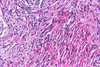

Scwhannomas……Histologically, they are characterized by compact, hypercellular areas of elongated cells called Antoni A bodies and loosely arranged hypocellular areas called Antoni B bodies. Antoni A bodies also tend to palisade around hypocellular areas called Verocay bodies (2 nuclear palisading bodies w/ hypo cellular center)

Neurofibroma -- dark nuclei with wavy dark nuclei in a fibrotic storm A: Schwannomas are the most common tumor of the peripheral nerves. They are made entirely of benign neoplastic Schwann cells. The presence of nerve fibers makes this answer incorrect. Answer B: Perineuromas are composed of only perineural cells. These can clinically mimic schwannomas. On pathology, there is pseudo–onion bulbing that differentiates it from schwannomas. (ONOION) Answer C: Ganglioneuromas are large slow-growing tumors that arise from sympathetic ganglion cells. The patient in this case has a tumor in her brachial plexus, which excludes this answer. (SYMPATHETIC!!!!)